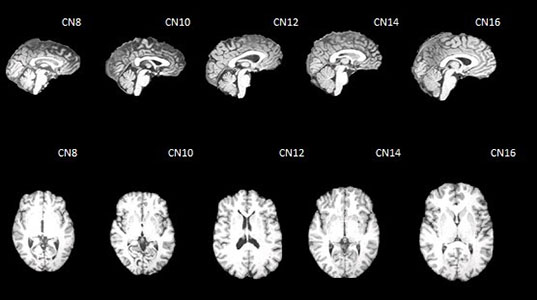

Chinese MRI Children Brain Templates

Wanze Xie, John, and Kang Lee are working on a on a project to create brain templates and atlas for...